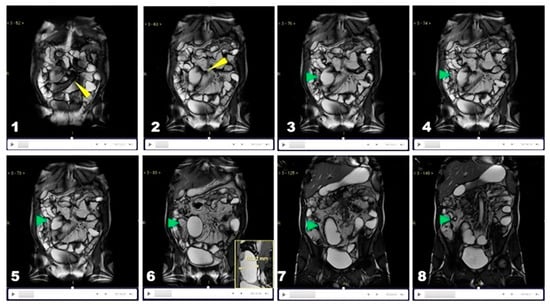

5.2. Stepwise Methodology